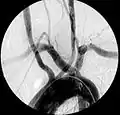

Aberrant subclavian artery

Aberrant subclavian artery, or aberrant subclavian artery syndrome, is a rare anatomical variant of the origin of the right or left subclavian artery. This abnormality is the most common congenital vascular anomaly of the aortic arch,[1] occurring in approximately 1% of individuals.[1][2][3]

This condition is usually asymptomatic.[1] The aberrant artery usually arises just distal to the left subclavian artery and crosses in the posterior part of the mediastinum on its way to the right upper extremity.[2] In 80% of individuals it crosses behind the esophagus.[2] Such course of this aberrant vessel may cause a vascular ring around the trachea and esophagus. Dysphagia due to an aberrant right subclavian artery is termed dysphagia lusoria, although this is a rare complication.[2][3] In addition to dysphagia, aberrant right subclavian artery may cause stridor, dyspnoea, chest pain, or fever.[1] An aberrant right subclavian artery may compress the recurrent laryngeal nerve causing a palsy of that nerve, which is termed Ortner's syndrome.[4]

The aberrant right subclavian artery frequently arises from a dilated segment of the proximal descending aorta, the so-called Diverticulum of Kommerell (which was named for the German radiologist Burkhard Friedrich Kommerell (1901–1990), who discovered it in 1936).[5][6] It is alternatively known as a lusorian artery.[1][3]